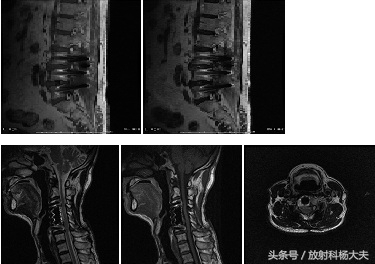

其实除了假牙,在磁共振的检查中,还有很多!如最常见的腰椎或者颈椎椎间盘手术,应用钛合金材料进行支撑或固定。由于其材质较好,图像伪影基本不影响诊断。(前提是得明确的知道这些植入物是能进磁场的,这很重要!)

有假牙头部做磁共振有影响吗,有假牙能做核磁共振全过程视频

从上图中可以发现,在颈椎及腰椎的固定术中,其所用材质较好,相对于假牙的不同材质,其对材质的要求比较严格,所产生的伪影较小,能够满足临床的诊断与鉴别诊断。